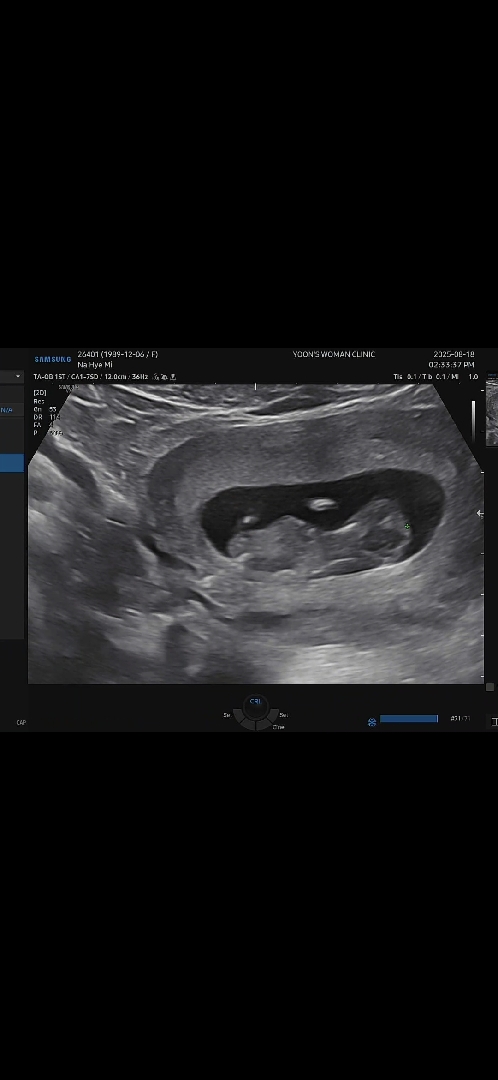

11주3일사진입니다 성별구분이갈까요?

아들?딸?